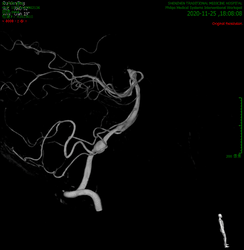

患者杜某,因反复出现后枕部疼痛而来我院就诊,在为其进行了颅脑血管增强CT(图1)、全脑血管造影术(图2)后发现,该患者后颅窝椎动脉V4段存在巨大的双侧椎动脉夹层动脉瘤(VADA),其中左侧较大,已近2cm,造影清晰后其中的血流涡流清晰可见,破裂风险很高,而因其紧邻脑干、小脑、后组颅神经等重要结构,一旦发病,致死率及致残率极高。

治疗前影像动图: